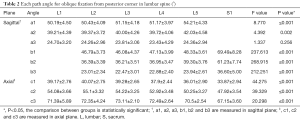

The angles of each path (Table 2)

Full table

The included angles a1, a2, a3, b1, b2, b3 and c1, c2 and c3 in the sagittal plane were significantly different (P≤0.001) (Figure 13) (a1 > a2 > a3, b1 > b2 > b3, c1 < c2 < c3). In the angles of sagittal down-path, b1, b2 and b3 change significantly and consistently, showing a trend of decreasing first and then increasing, which is the smallest at L3 (46.08±4.37°, 36.21±3.51°, 22.47±3.01°) and the largest at S1 (69.49±8.28°, 61.23±7.74°, 36.60±5.00°). In the angles of sagittal up-path, a1 and a2 change in the same way, showing an increasing trend. While a3 goes down and then goes up, which is the smallest at L4 (23.43±4.29°) and the largest at L5 (24.36±2.94°). In the angles of axial plane, c1, c2 and c3 change in the same way, showing a trend of increasing first and then decreasing. c1 and c2 are the largest at L2 (40.07±2.75°, 55.1±3.32°), and c3 is the largest at L3 (73.11±2.10°). c1, c2 and c3 are the smallest at S1 (33.87±2.94°, 47.92±3.54°, 67.15±3.60°) (Figures 14,15).